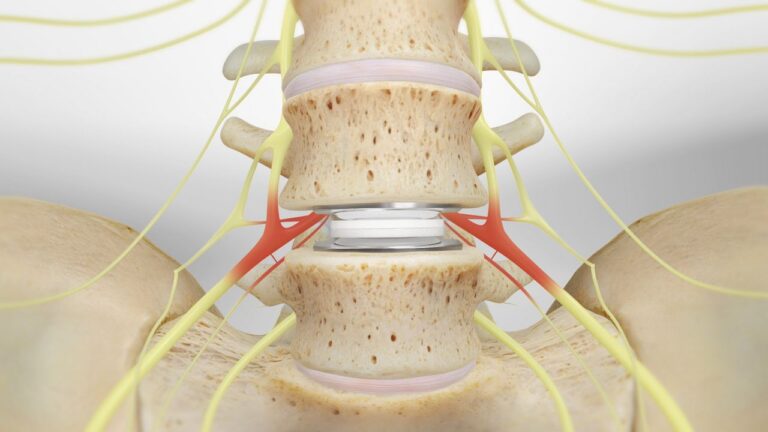

عملية الغضروف: عملية الانزلاق الغضروفي بالمنظار وكم مدة التعافي بعدها؟

عملية الانزلاق الغضروفي بالمنظار، الانزلاق الغضروفي يعتبر أحد أمراض العظام والذي يصيب الغضروف ما بين الفقرات تحديدا ويؤثر…

ما هي أنواع مرض الغضروف؟